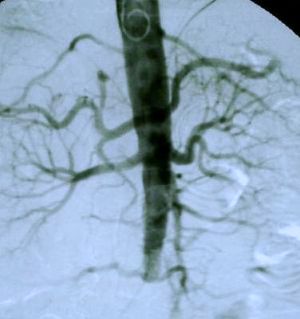

Aortic angiogram of patient showing iliac arteries tapering off to nothing

Fig 2. Abdominal aortic angiogram

With their usual enthusiasm, the vascular surgeons obtained a gated radionuclide cardiac ejection fraction (MUGA scan) which returned a value of 25% (Normal value: > 50%). They also obtained an angiogram of the abdominal aorta, shown in figure 2.